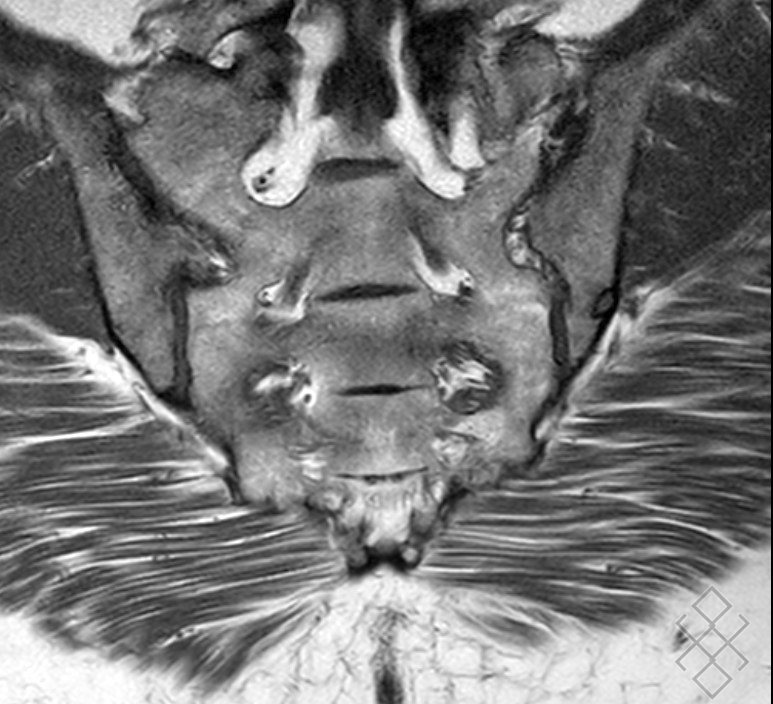

Sacroiliite droite. Sclérose souschondrale (bande hypointense). IRM,... Download Scientific. IRM du bassin avec atteinte dégénérative et inflammatoire des sacro iliaques Le positionnement de l'aiguille est en effet délicat et il est fréquent que l'injection ne soit.